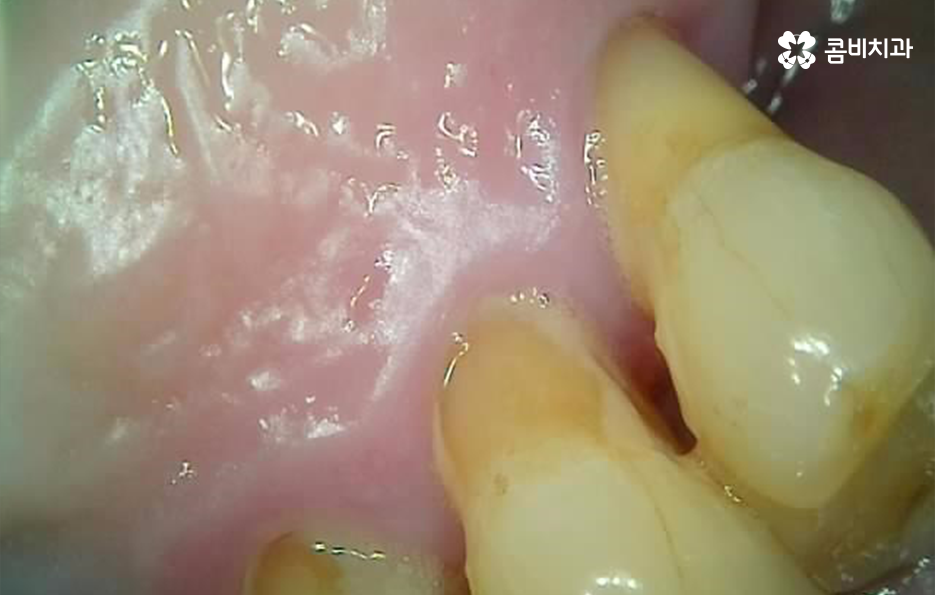

그 중에서도 치주염으로 인해 위에 보시는 사례 사진처럼 잇몸은 내려앉고 치아 뿌리가 외부에 상당 부분 드러나는 경우에는 우선 일상에서 치아가 무척이나 시리고 통증을 느끼게 되며 치주염이 결국 잇몸 뼈를 녹게 만들어서 치아 뿌리가 흔들리고 결국 발치하게 되는 경우가 많아요